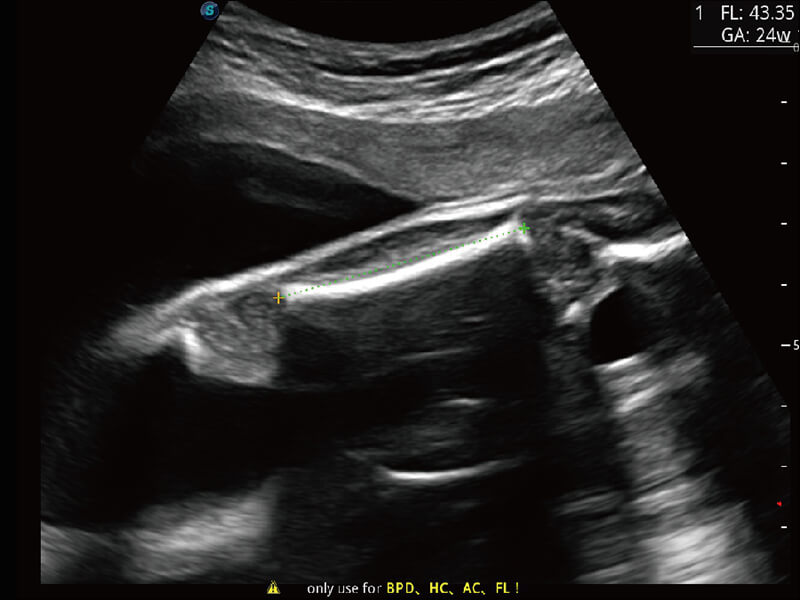

性能优异的硬件架构,极大提升超声系统的运行效率和数据处理能力。相比以往超声成像系统,Wis+平台为您带来极快的响应速度和成像帧频,提升检查流畅度。

S60探头工艺,从前端信号处理每一个环节采集无损声学数据,真实还原组织原貌,再现解剖细节。

超宽频带技术,为容积成像带来优质的二维图像基础,为您呈现丰富的结构细节,栩栩如生地展示宝宝的宫内形态以及各种组织的立体结构。